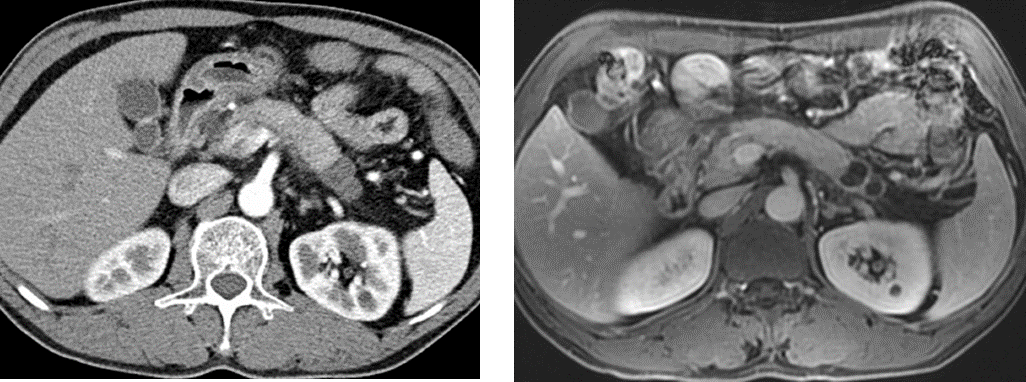

T1WI:实性占位

图5 实性浆液性囊腺瘤(SCN) T1WI显示病灶明显优于T2WI

(图片来源:余日胜教授讲课使用)

02

T2WI:囊性占位及纤维分隔

图6 胰腺囊性病灶及纤维分隔:T2WI